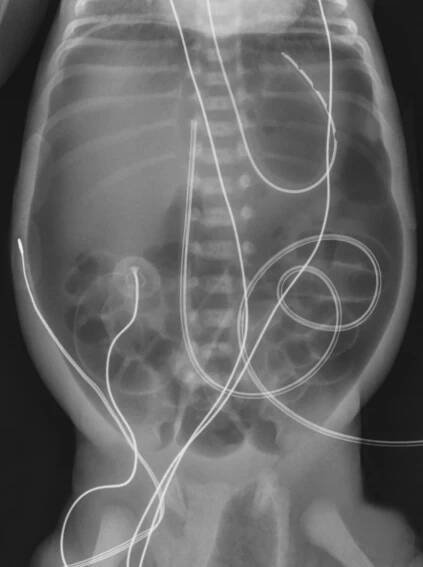

Česká Neonatologická Společnost • RTG abdomen 07 pneumoperitoneum

Spontaneous Intestinal Perforation | Applied Radiology